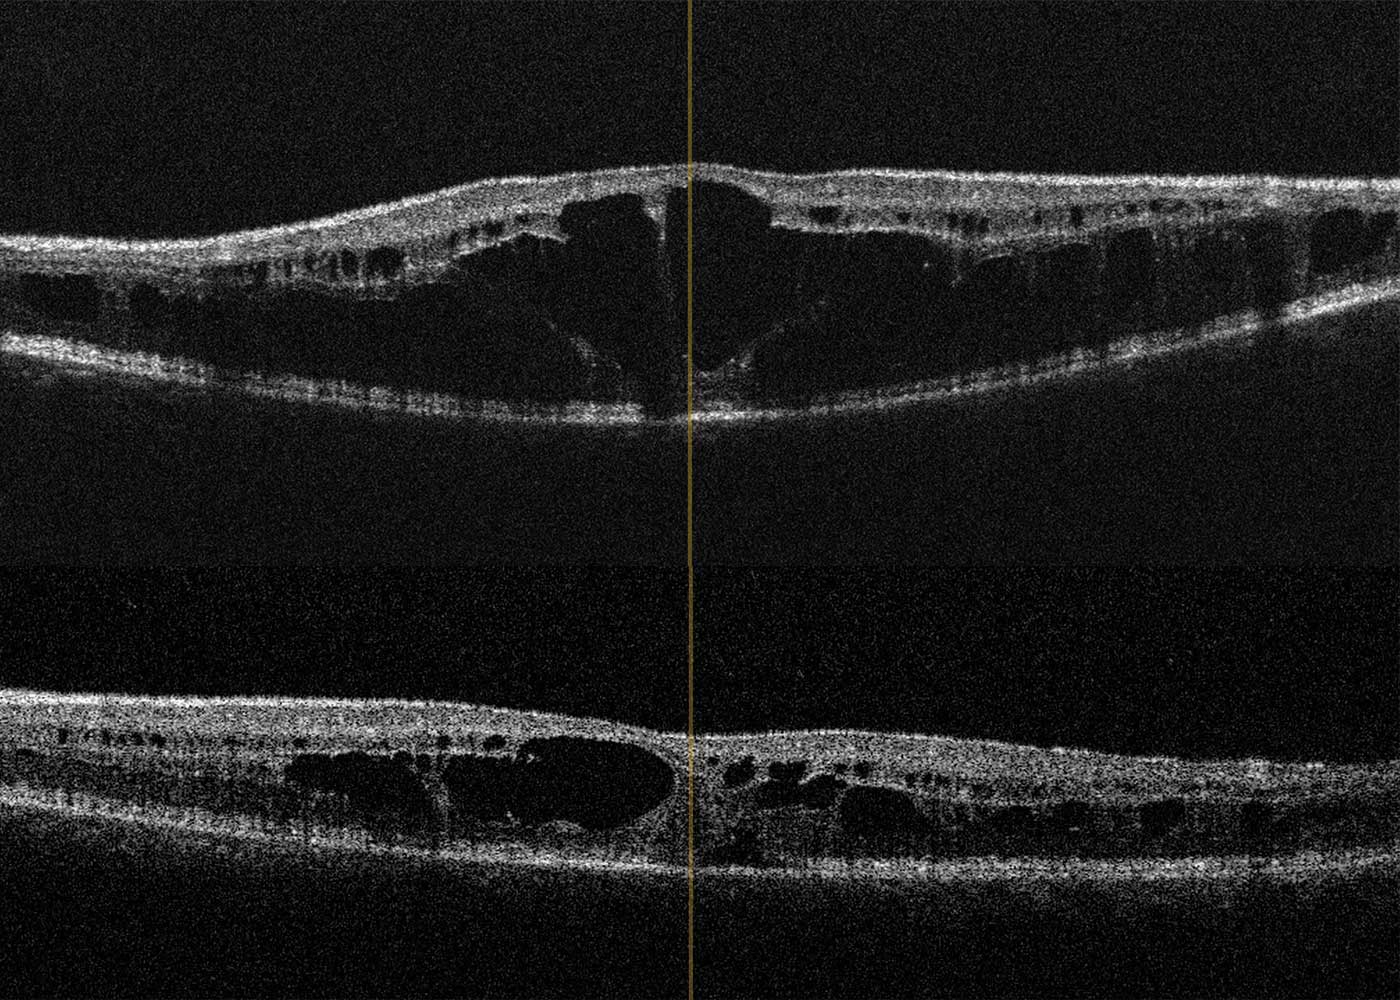

A 14-year-old boy and his parents came to the clinic for the first time for a co-assessment of increasing visual deterioration on both sides. He had been examined regularly by an ophthalmologist, who detected non-specific progressive retinal changes which had not been further clarified. During the first appointment, the visual acuity was 0.6 on the right and 0.1 on the left eye. Funduscopic examination revealed pigment epithelial clumps of the peripheral retina in the form of bone trabeculae on both sides and fluorescence angiography revealed a discrete but clinically significant diffuse macular oedema. In contrast to the findings described in case 1, OCT of the macula showed large, bubbled cystoid changes on both sides with angiographically proven intraretinal fluid as oedema (Figure 4). The colour vision test panel D15 was unremarkable and there were no changes in the outer visual field borders on either side. No other affected family members were found in the family history. Here, too, the patient was brought to the human genetics clinic and a panel diagnosis (Sanger sequencing) was initiated for suspected rod-cone dystrophy in the index patient.

Due to the fluid-filled intraretinal cysts found angiographically, a therapy with a carbonic anhydrase inhibitor (initially systemic, after 4 weeks as local therapy) was started.22 This resulted in a visual acuity gain to 0.4 in the left eye with visual stabilisation in the right eye due to a significant reduction in intraretinal fluid, especially on the left (Figure 5). At the same time, electronic equipment for digital magnification were arranged for the school in addition to special workplace lighting.

In contrast to this case report, in case report 2 there were no ground-breaking indications due to a conspicuous inheritance. In this case, the molecular genetic panel diagnostics was helpful due to the cone-rod dystrophy, which could be diagnosed with clinical certainty.20,21 Whereas in case report 1 the cleft formation of the foveola was caused by a disorder of cell-cell interaction and cell adhesion of the inner retina, in this case report fluorescence angiography demonstrated clinical macular oedema (Figure 4b). After referral to a centre experienced in gene therapy for hereditary retinal dystrophies, a therapy with carbonic anhydrase inhibitors was started, which at the present time has resulted in an improvement in the findings.22